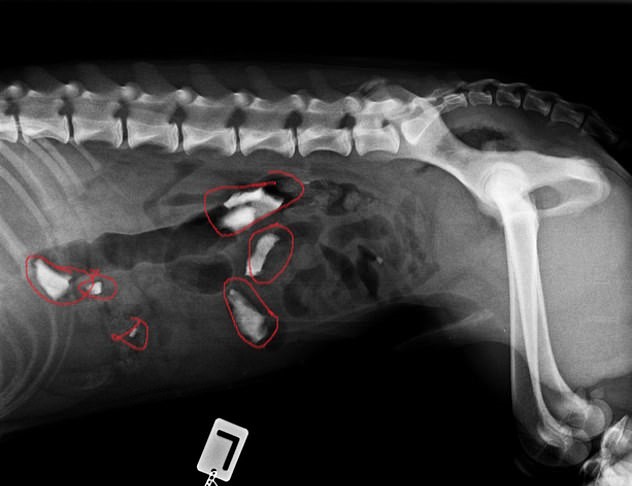

Previously, Dexter had four surgeries to remove foreign objects from his stomach.

“On four occasions, Dexter required an exploratory celiotomy, which is when a large incision is made down the tummy to identify all the organs within the body,” veterinarian Sebastian Griffin said.

“Once the foreign bodies are located the intestines are incised, the foreign body removed and then the intestines are stitched back together.”

As he added, the foreign objects included duct tape, a tennis ball, a plastic bag, fishnet tights, and wood chippings. On one occasion, Dexter also swallowed chocolates that could have easily ended his life if not detected in time.